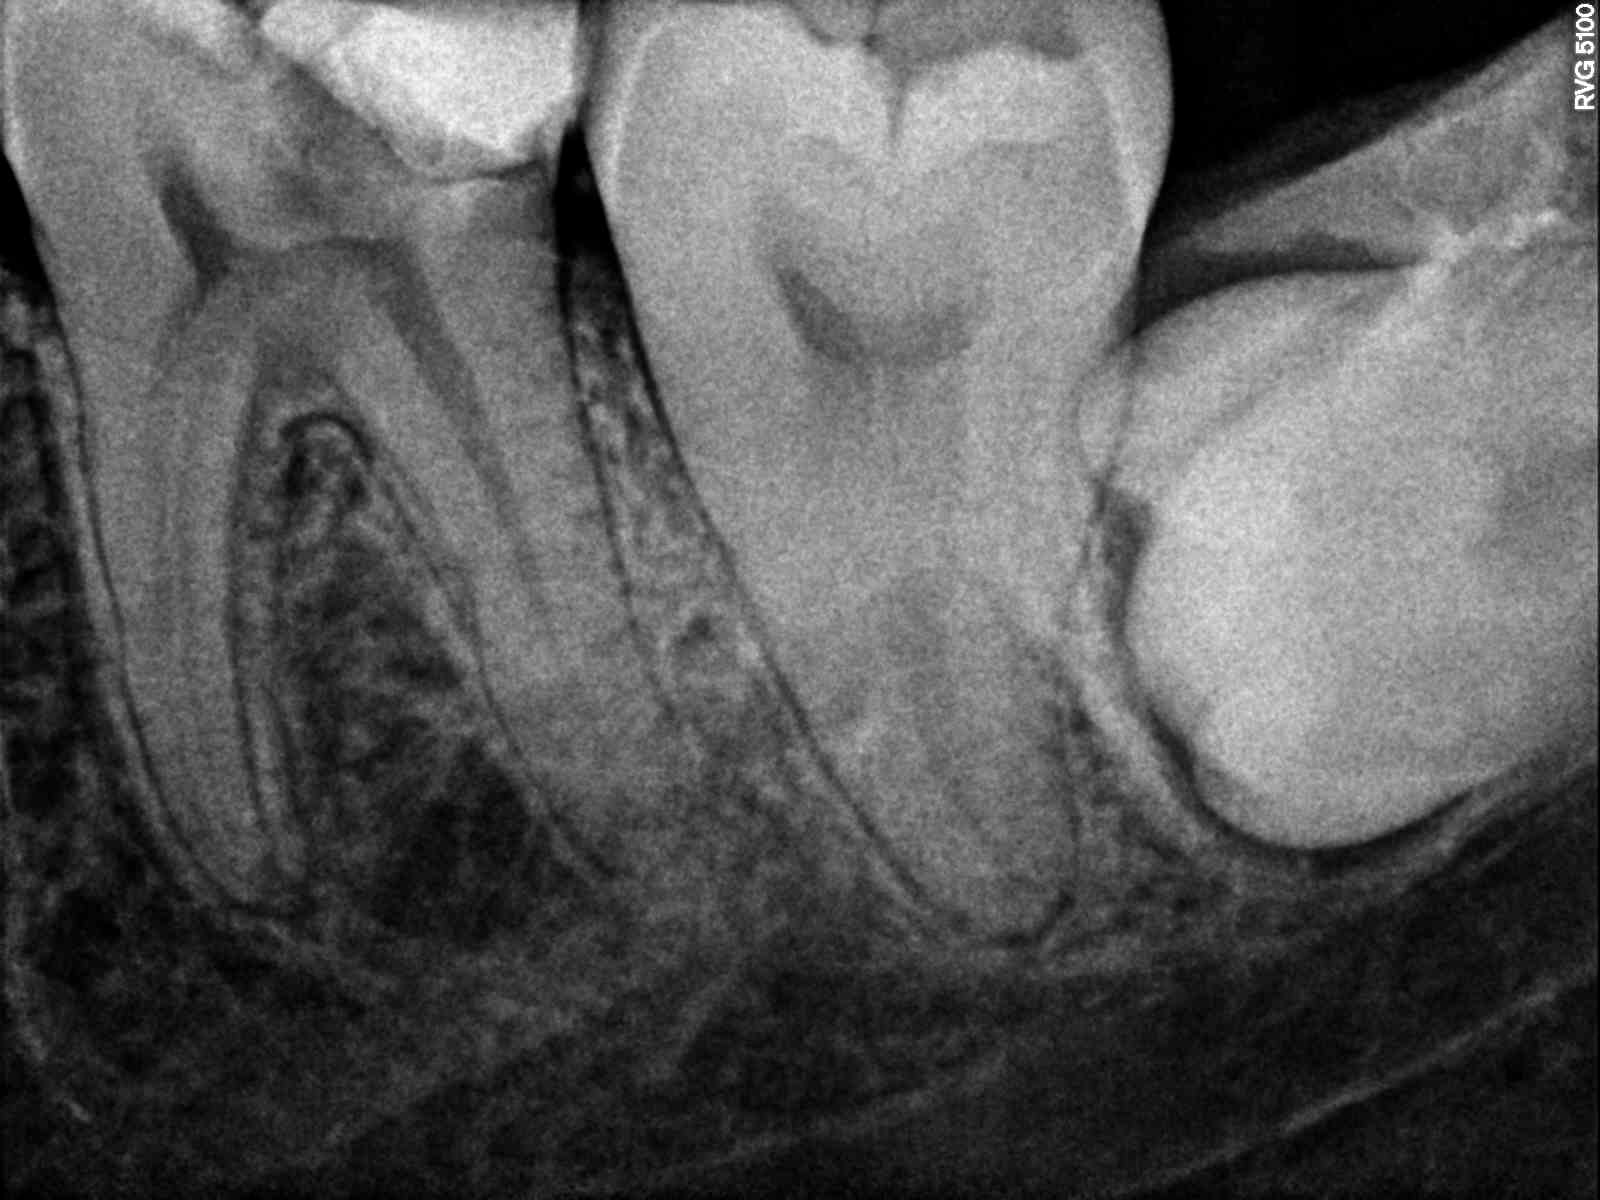

Il s'agit d'une 36 atteint d'une pulpite sur laquelle j'ai fait l'endo.

Entre le traitement initial et la pose de l'inlay-core il s'est passé environ 3 semaines durant lesquelles le patient a maché sur une provisoire sans douleur ni gêne.

Malheureusement c'est après avoir scellé l'inlay-core et appuyé dessus que je me suis rendu compte que le patient avait mal et que çà durait depuis 2 jours...

La douleur est seulement à la pression/percussion.

Depuis j'ai remis une provisoire en sous-occlusion et en une semaine la douleur est la même aucun changement (pas de bourrage pas de surocc).

J'ai l'impression qu'il y a une fracture en mésial mais qu'elle se soit produit en inter-séance me laisse perplexe.

Sur la dernière radio on voit un épaississement.

Qu'en pensez-vous ?

Anatomie de la racine distale avec un pincement au centre de la racine. La préparation à affaibli la racine et l'inlay-core a fracturé cette zone de plus faible épaisseur.

Sur la radio, on a l'impression de voir un pincement comme dans une forme en huit mais seulement sur la partie mesiale de la racine distale.

Et un trait de fracture à mi-hauteur de la ou des racines M, sur les radios 2 et 3, avant et après l'inlay-core?